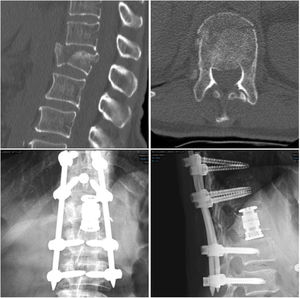

En los pacientes de mayor edad y con mayor riesgo quirúrgico, se prefiere fijación percutánea posterior en decúbito prono dos niveles por encima y dos por debajo junto a vertebroplastia de la vértebra fracturada (técnica 2) (fig. 3).